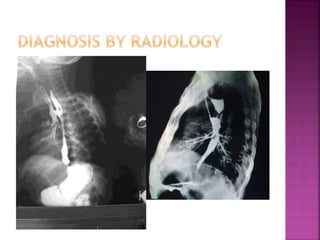

• High variety of malformation 

If the rectum is blind ending above the

levator funnel.

• Low variety of malformation 

If the rectum passes through the anorectal

pouch opens out on the skin either at the site of the

anus or anteriorly on the perineal or scrotal raphe

in the male or in the vestibule or vulva in the

female.

• Intermediate variety  Fistula to the posterior

urethra in the male , or vestibule in a female.

• High varietyof malformation  If the rectum is blind ending above the levator funnel. • Low variety of malformation  If the rectum passes through the anorectal pouch opens out on the skin either at the site of the anus or anteriorly on the perineal or scrotal raphe in the male or in the vestibule or vulva in the female. • Intermediate variety  Fistula to the posterior urethra in the male , or vestibule in a female.